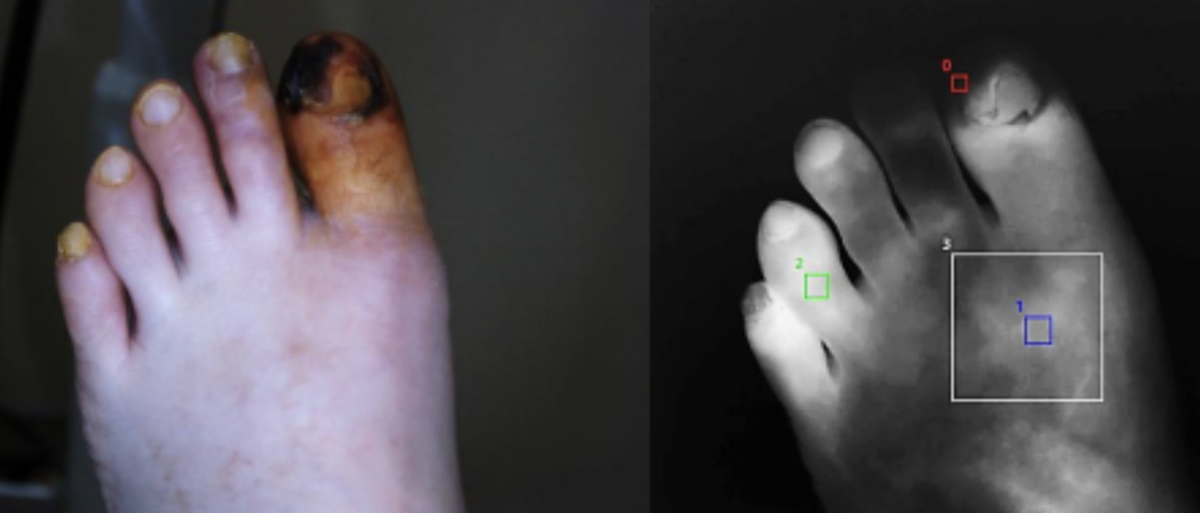

Изображение с экрана монитора системы «МАРС», флуоресценция с красителем Индоцианин зеленый.

При внутривенном введении контрастного препарата (Индоцианин зеленый – ICG) под воздействием лазера в ближнем инфракрасном диапазоне сосуды становятся визуально доступными, данный процесс называется флуоресценцией. Врач фиксирует участки с различной степенью кровоснабжения. Однако визуальной оценки может быть недостаточно для принятия решения о необходимости оперативного вмешательства или отслеживания динамики состояния. В таких случаях нужны количественные параметры интенсивности флуоресценции.

Количественная оценка кровоснабжения у пациентов с клинической ишемией нижних конечностей позволяет получить объективное представление о состоянии артерий.